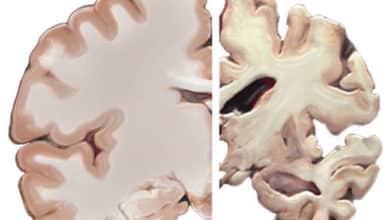

ألزهايمر Alzheimer’s disease

دراسة: أجزاء من الدماغ قد تكون محصنة ضد مرض ألزهايمر

كجزء من رسم أكبر خريطة على الإطلاق للدماغ البشري تحت تأثير مرض ألزهايمر، وجد الباحثون مزيدًا من الأدلة على أن…